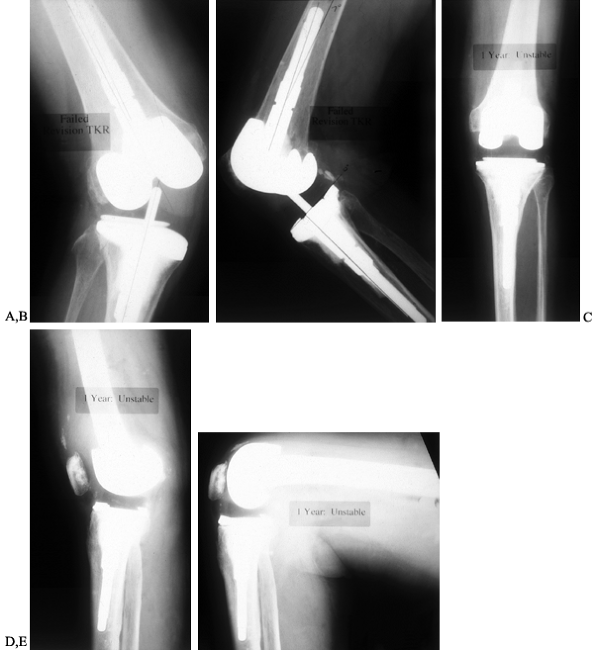

Figure 109.4. AP (A) and lateral (B)

radiographs of an 83-year-old woman with valgus instability in a revision arthroplasty despite the use of a constrained condylar implant. The problem results from loss of ligamentous integrity, combined with malalignment that increases the deforming force on the polyethylene of the tibial component. Weight-bearing AP radiograph (C) of a 71-year-old woman with a nonconstrained posterior stabilized implant showing good stability in the varus and valgus planes. Lateral weight-bearing radiograph (D) showing hyperextension. This patient had failure of the posterior structures as a result of spinal stenosis and weakening of the extensor mechanism, which caused her to walk with recurvatum to prevent buckling. Lateral radiograph in flexion (E) showing that the flexion gap remains stable. |